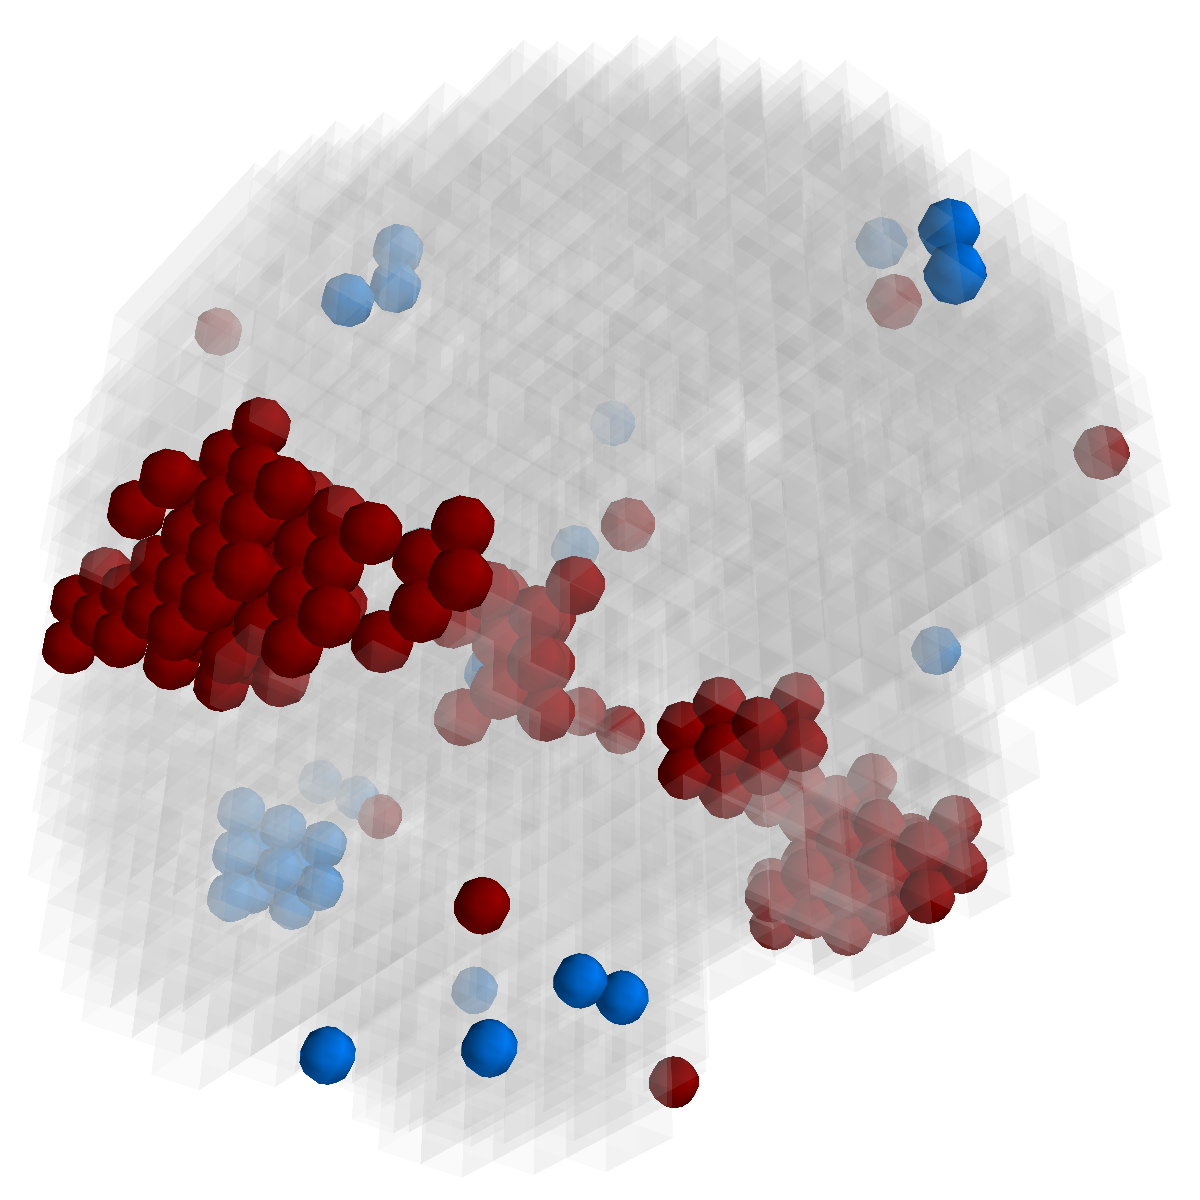

Figure 3: Stability of selected voxels across different folds of the cross-validation. The results of 5 different folds are shown in (a)-(e). The voxels with positive β𝛽\beta are in brown, negative ones are in blue. The common/overlapped voxels selected in all 10 folds are shown in green (f). The top row illustrates voxels selected by the lasso model, the mid row illustrates those of GFL and the bottom row shows those of n2superscript𝑛2n^{2}GFL.

Feature Stability. In Figure 3, we show the selected voxels across different folds of CV333Here, parameters were determined by accuracy. Similar results were observed using parameters producing same level of sparsity.. As shown, the selected voxels by lasso vary much across different folds, whereas the selected voxels by GFL are more stable. However, by assuming the positive correlation between the features and the disease labels in n2superscript𝑛2n^{2}GFL, we further increase the stability. To quantitatively evaluate the stability gain, we denote the variables of the k𝑘kth fold of CV as 𝜷(k)𝜷𝑘\boldsymbol{\beta}(k). We introduce two measurements here. In (?), the Estimation Stability (ES) is proposed to measure the stability of the estimation

where ##\# is the number of elements in a set. In Tab. 3, both measurements quantitatively suggest n2superscript𝑛2n^{2}GFL obtains much more stable voxels due to the consideration of the correlation between the features and the disease labels 444We notice that, in (?), the stability is computed using the top 50 positive voxels because these voxels are believe to be the most atrophied ones. By computing the stability of all non-zero voxels, the mDC of GFL drops around 30%percent3030\%. This clearly shows that the instability is caused largely by the undesirable voxels that disagree with the correlation prior (those scattered blue voxels in the mid row)..